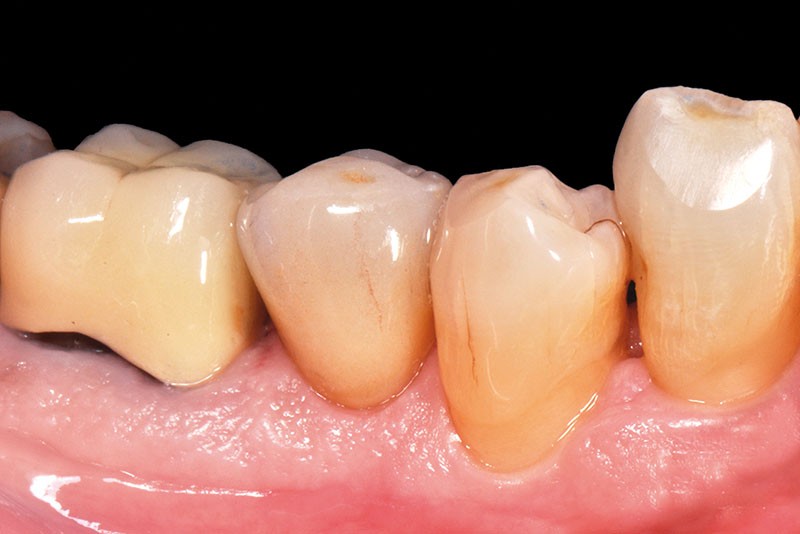

34, 35. Vues vestibulaire et occlusale de la prothèse d’usage collée sur 45 (Laboratoire du Sud-Ouest).